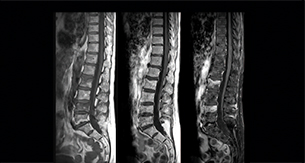

“In our spine cases, we use mDIXON TSE for patients with degenerative and inflammatory spine issues, vertebral fractures and vertebral and paravertebral tumor characterization,” says Dr. Lefebvre. “It provides, in a single acquisition, different contrasts so we can both visualize and characterize spinal, focal or diffuse spine lesions.”

“mDIXON TSE makes real a difference in cases of acute and traumatic spinal injuries, where it allows us to reduce the scan time by only using a limited number of sequences. For patients in pain, who come from the emergency unit and need surgery, for example, MRI must be very fast. With a single T2-weighted acquisition we can assess spinal cord, vertebral disc and ligament wholeness with in-phase images, as well as trabecular fracture and edematous changes with water images.” Dr. Lefebvre cites other frequent examples of spinal diseases that benefit from the mDIXON technique. “In cases of vertebral disc herniation or degenerative discs, for example, we don’t have to choose between fat or no fat images. We can assess morphological changes in the endplate with in-phase images from T2-weighted sequences and in the water image from the same acquisition we will see inflammatory changes into endplates.”